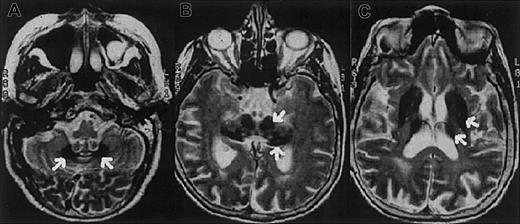

The proband is a 62-year-old Italian woman. No family history of diabetes, iron overload, anemia, or neurologic disorders was recorded. At age 38 years the patient developed insulin-dependent diabetes mellitus. A mild degree of anemia (hemoglobin 9.1 g/L) with normal mean corpuscular volume (MCV; 86 fL) and low-normal values of mean corpuscular hemoglobin (MCH; 27.2 pg) and mean corpuscular hemoglobin concentration (MCHC; 31.7 g/dL) was documented at age 51 years. Serum iron concentration was 33 μg/dL, transferrin saturation 12%, and serum ferritin 819 μg/L. Bone marrow aspirate revealed mild dyserythropoiesis; iron staining showed abundant iron in RE cells and absence of iron granules in erythroblasts. Moderate anemia and abnormal iron parameters without evidence of blood losses or inflammatory diseases were regularly observed at follow-up. Ataxia, dystonia, mild parkinsonism, and dementia became evident at the age of 62 and progressed rapidly. Magnetic resonance imaging of the brain showed a paramagnetic deposition in the basal ganglia, dentate nucleus, thalamus, substantia nigra, and cerebral and cerebellar cortex (Figure1). Serum Cp was undetectable. Liver function tests were normal. No Kayser-Fleischer ring was observed, but the retina showed a pigmentary degeneration.

Magnetic resonance images of the proband showing iron deposition in the brain.

Axial T2-weighted magnetic resonance images of the proband's brain show low-signal areas (arrows) in the dentate nucleus (A), red nucleus and substantia nigra (B), and corpus striatum and thalamus (C), which suggest iron deposition in these regions.